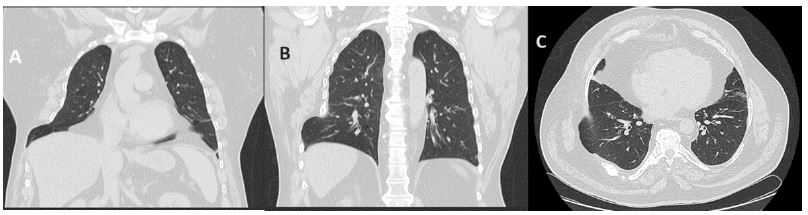

Lung hernias result from the protrusion of part of the lung parenchyma through the rib cage. They can occur after trauma or as a post-surgical iatrogenic, but spontaneous occurrences is very rare [1]. The authors present a case of a 57-year-old man, former smoker, overweight, with obstructive sleep apnea. He went to hospital with one-week history of dry cough, with no other associated symptoms, no alterations on physical examination or significant analytical changes. A viral infection was assumed. He came back five days later with chest pain and swelling in the right latero-basal region, worsened by coughing. Objective examination revealed a hematoma at that location. A chest CT scan showed 7th costal arch’s fracture and a right lung herniation in this area (Figure 1).

Figure 1: Coronal (A and B) and axial (C) chest CT scan, showing fracture of the 7th costal arch and an exuberant right lung herniation in that region.